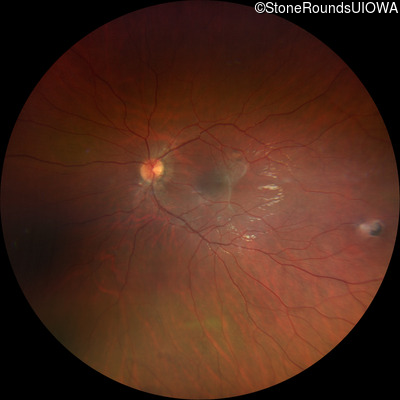

This 9 year old male was noted to have some crossing of his eyes at 2 months of age and the eye exam which followed identified a retinal lesion in the right eye. When he was six years old an epiretinal membrane was noted in his left eye. Two years later it was decided that it was a thin hamartoma in that eye as well. He underwent neuroimaging at age 7 which identified bilateral acoustic neuromas.